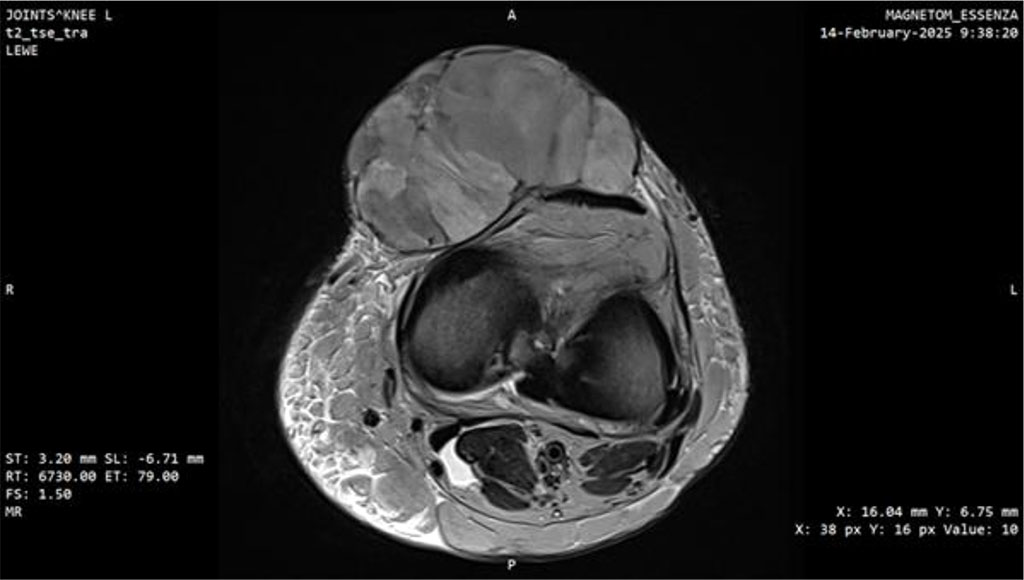

At this point, the patient was transferred to a center of the highest reference, specializing in sarcomas. MRI performed there demonstrated a well-defined, heterogeneously enhancing solid mass measuring 77 × 45 × 78 mm with surrounding fat stranding. A repeat biopsy was performed, and the third histopathological result confirmed myxofibrosarcoma, FNCLCC grade 3 (Fig. 3, 4).

Figure 4: MRI scan of the knee joint with Myxofibrosarcoma (MFS). Axial plane.